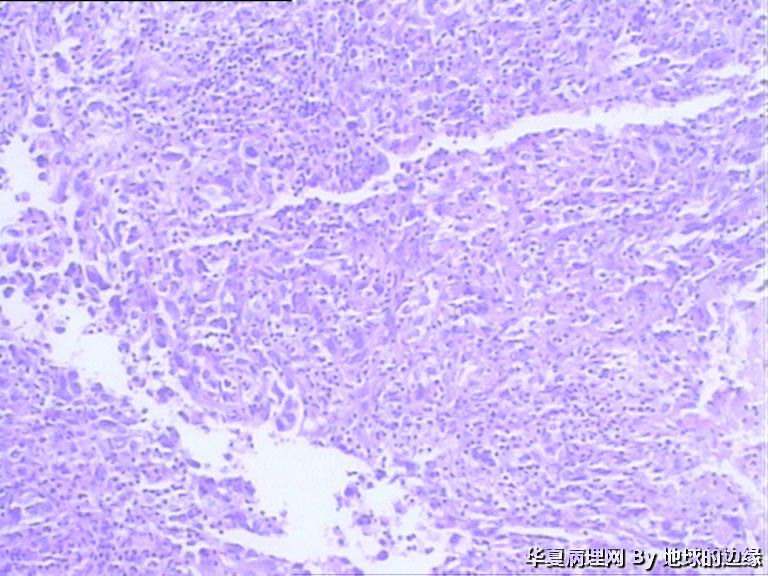

病人女性,48岁

MRI示:右肱骨肿瘤待排,包块大小为10x8cm,活动度差,边界欠清,鱼肉组织(白色),肿块侵犯至骨外    组  织。

恶性。是转移还是原发,是骨肉瘤还是浆母?需要进一步资料并标记。

考虑肉瘤,转移癌也排除一下吧

目前Vimentin阳性,P53阳性,AFP,EMA,CK7,CK20,E-ca,CR,PLAP,CD99,ER,PR,CEA,均阴性,只是没做淋巴瘤这一套了